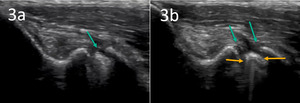

When evaluating a UCL tear with MSK-US, one may observe a widened UCL or redundant folds, irregular hyperechoic structures, clefts or gaps in the ligament coaptation line, discontinuity of continuous fibers within the UCL fibers, or pseudo fluid collections at some locations with laxity. Discontinuity appears as an apparent tear or gap between the proximal and distal ends of the tendon/ligament with intra-tendinous hyperechoic areas. A high-resolution MSK-US image can also reveal other pathologies such as tendinopathies, swelling, joint effusions, and cartilage lesions. Tendinopathy consists of irregular fibers within affected muscles or tendons and occasionally thickening around the tendon which may present with hypoechoic regions. Debris in a joint space indicates foreign bodies such as bacteria or nutrient crystals which can cause inflammation and damage to the surrounding tissue. MSK-US can help differentiate these pathologies from chronic disruptions such as UCL tears or instability events. By accurately isolating these imaging findings together with the history and physical examination, MSK-US can safely diagnose and monitor musculoskeletal disorders providing accurate guidance for treatment options.